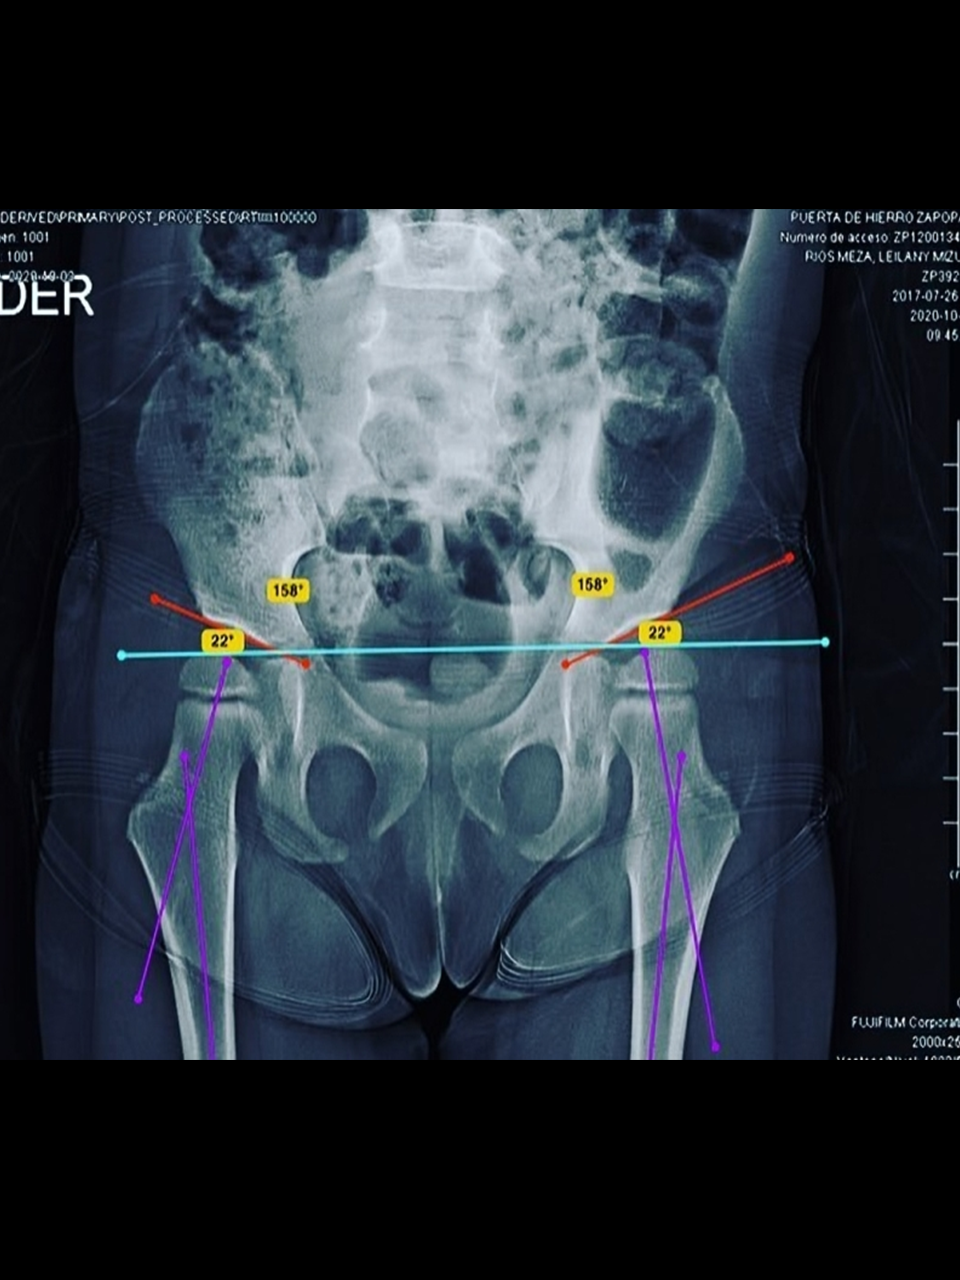

• Deformidades torsionales de tibia y fémur

• Displasia del desarrollo de la cadera y tamiz de cadera